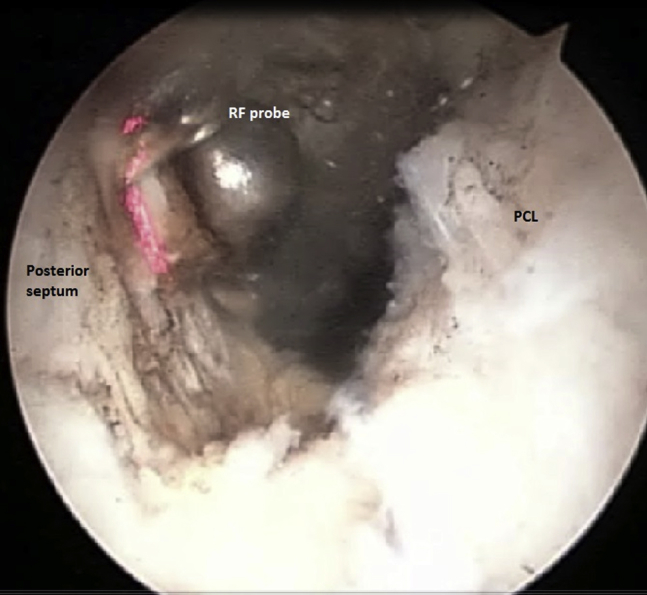

Fig 7.

Arthroscopic view from posteromedial portal in left knee joint. The radiofrequency (RF) probe, introduced through the posterolateral portal, is used to remove the rest of the posterior septum. (PCL, posterior cruciate ligament.)